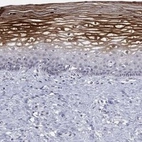

Immunohistochemical staining of human cervix, uterine shows strong positivity in squamous epithelial cells.